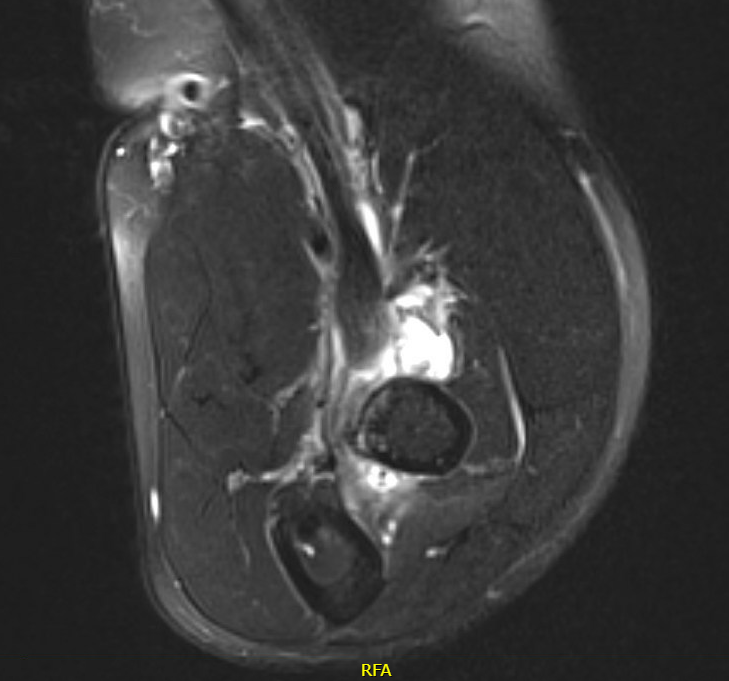

B.  Partial tear

Best evaluated on the axial view

- absence of low signal intensity biceps tendon insertion onto tuberosity

- present of soft tissue edema

MRI Biceps Partial TearBiceps Partial tear